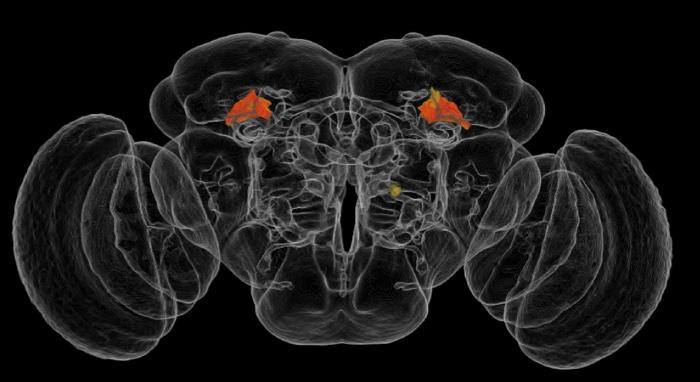

AI Imaging Tech Create ‘Brain Atlas’ Fruit fly brain image Robie et al HHMI

#AI#machinelearning#ML#neuroscience#science#tech https://www.laboratoryequipment.com/article/2017/11/ai-imaging-tech-create-brain-atlas …pic.twitter.com/cSJsighGqg ಧನ್ಯವಾದಗಳು. Twitter ಇದನ್ನು ನಿಮ್ಮ ಕಾಲರೇಖೆಯನ್ನು ಉತ್ತಮಗೊಳಿಸಲು ಬಳಸುತ್ತದೆ. ರದ್ದುಗೊಳಿಸು